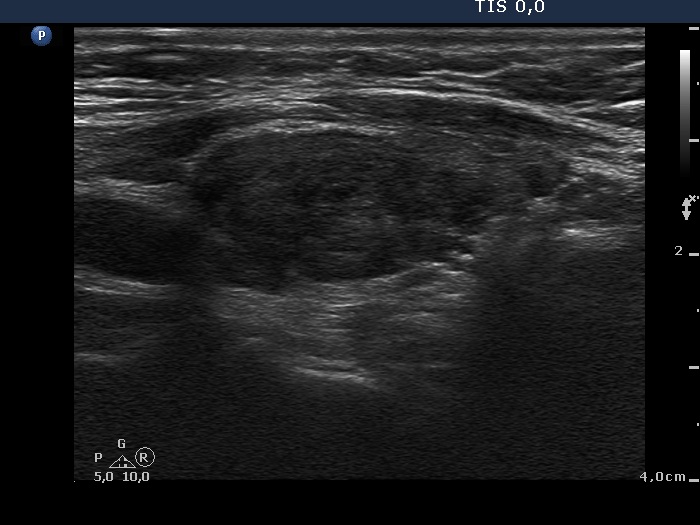

Ultrasonography. Both lobes were hypoechogenic and contained several hypoechogenic areas do not corresponding to nodules. The echogenicity index was 20%. The vascularization was a bit increased.

Aspiration cytology was performed from one of the hypoechogenic areas in the right thyroid and resulted in benign, hormonal atypia.